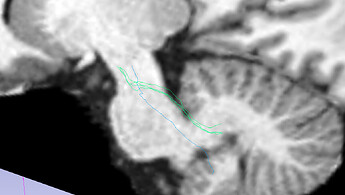

SCP:

Changing the step size (I have gone down to 0.01; screenshot above) does not have the impact that I would hope for a large change.